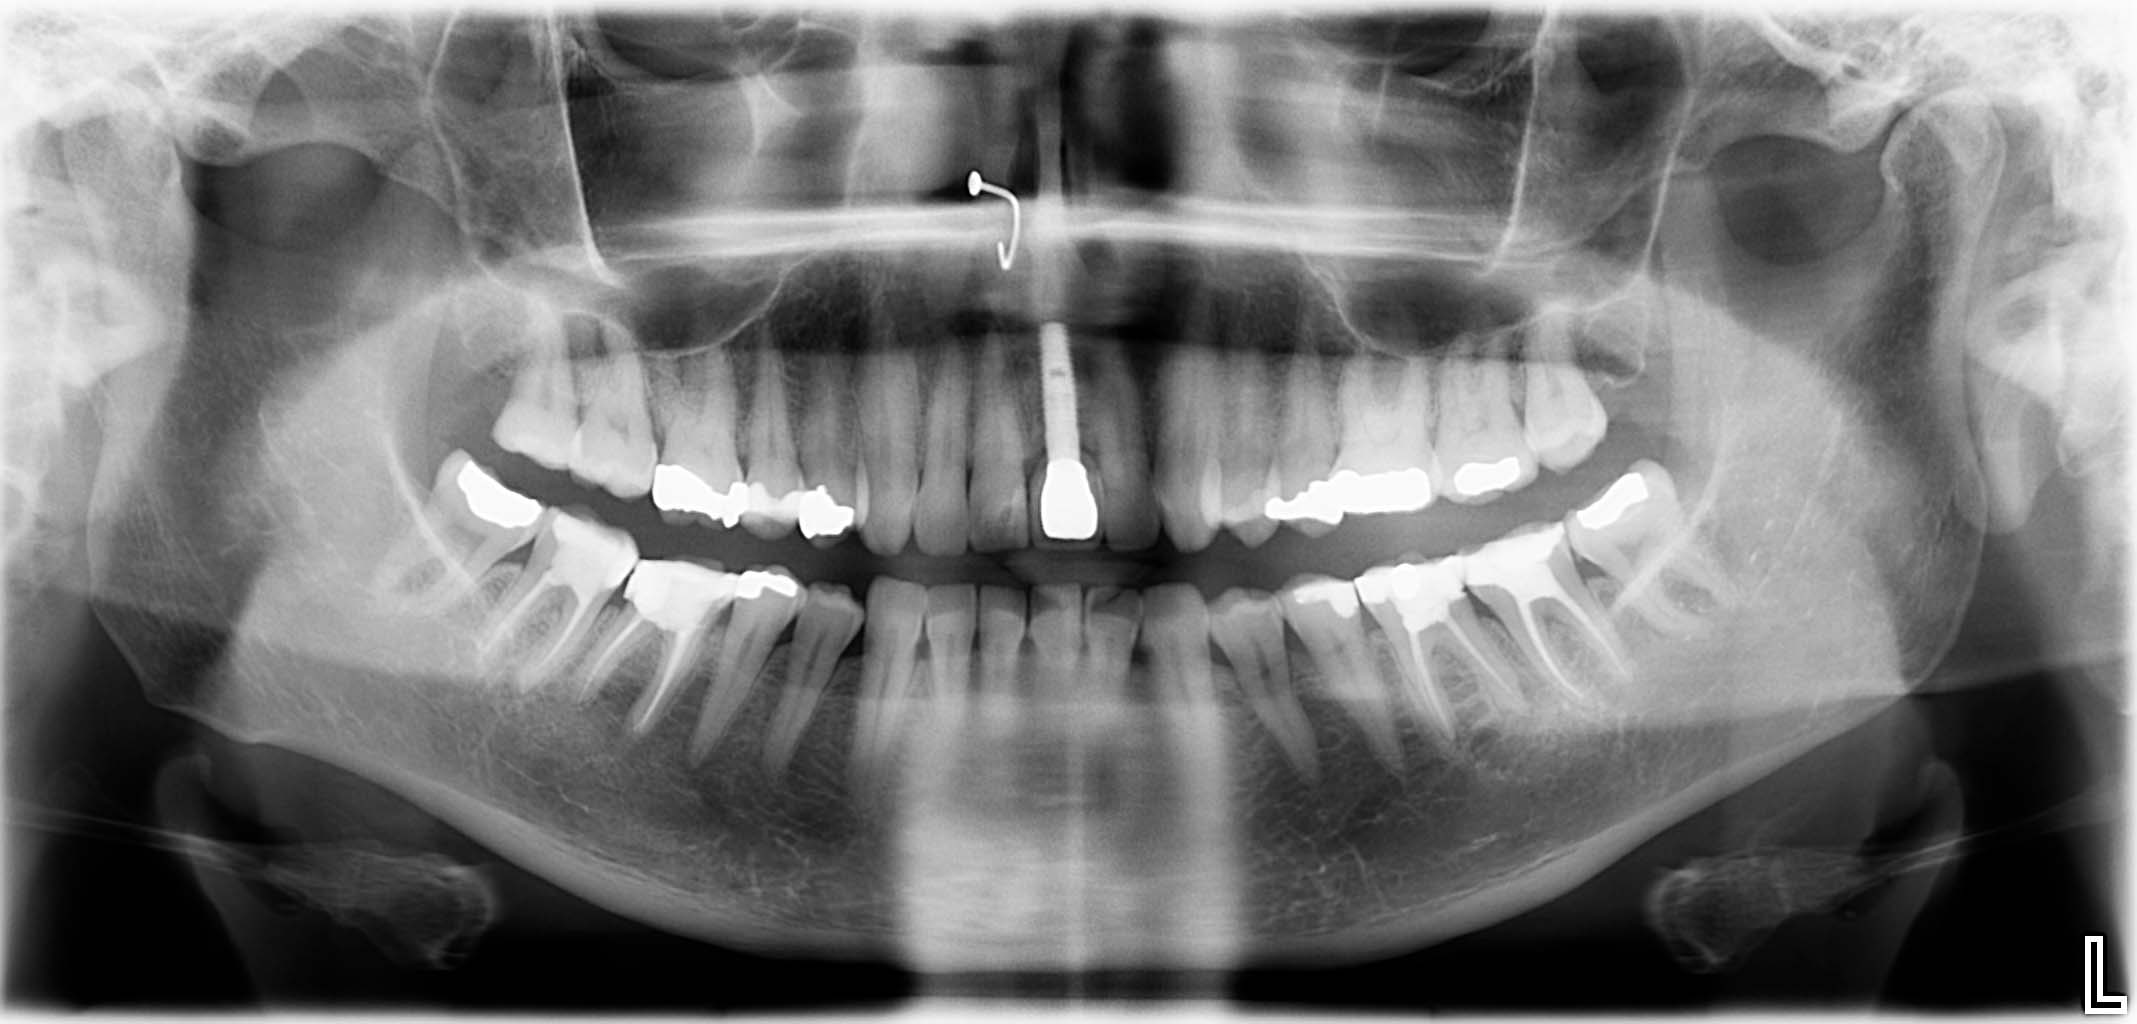

Erfolgreich implantierte Patientenfälle (klinische Fotos)